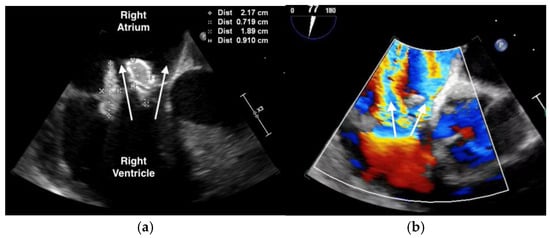

The purpuric rash was clinically consistent with leukocytoclastic vasculitis per dermatologic consultation, although a skin biopsy was not performed. A transthoracic echocardiogram showed normal ejection fraction, but revealed a large tricuspid valve (TV) vegetation (Video S1). A transesophageal echocardiogram confirmed large, multilobed vegetations on the TV measuring 1.9 cm × 0.9 cm on the anterior leaflet and 2.2 cm × 0.7 cm on the posterior leaflet associated with severe tricuspid regurgitation (Figure 2, Videos S2 and S3). (For a video of the transesophageal echocardiogram with cardiologist commentary, see Video S4.)

Figure 2. Transesophageal echocardiogram showing: (a) large, multi-lobed tricuspid valve vegetations associated with valve perforation and (b) severe tricuspid valve regurgitation (white arrow).